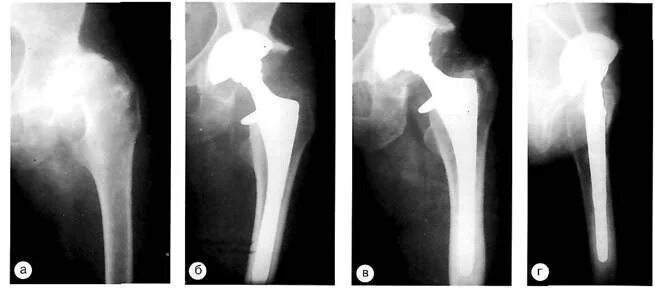

Нестабильность тазобедренного сустава